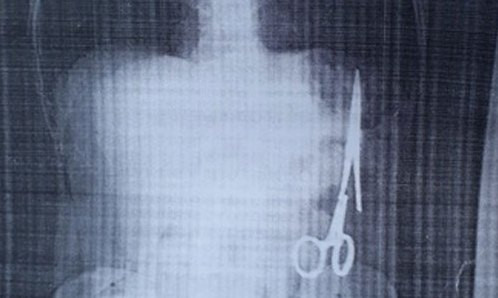

Mới đây ông Ma Văn Nhật, 54 tuổi, ở Bắc Kạn vào Bệnh viện Gang thép Thái Nguyên khám sau một lần thấy đau nhói ở bụng. Kết quả siêu âm phát hiện một chiếc panh dài khoảng 15 cm trong bụng.

Theo ông Nhật, trừ lần phẫu thuật cách đây 18 năm, ông chưa phải vào viện mổ lần nào nữa. Khi đó là tháng 6/1998, ông bị tai nạn giao thông khiến ghi đông xe đâm vào mạng sườn, được chuyển từ bệnh viện huyện ra bệnh viện đa khoa tỉnh Bắc Kạn và được chỉ định phẫu thuật. Sau mổ, ông vẫn ăn uống và sinh hoạt bình thường.

Sở Y tế Bắc Kạn cho biết có thể sẽ phẫu thuật lấy dị vật cho bệnh nhân tại Bệnh viện Gang thép Thái Nguyên. Các chuyên gia của Bệnh viện Hữu nghị Việt Đức có thể sẽ được mời tham gia ca mổ này để đảm bảo an toàn cho người bệnh.